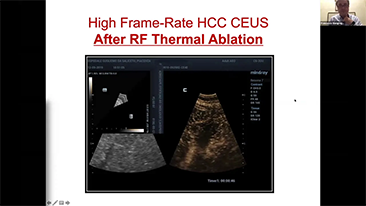

Hoe duidelijk is een lever te zien?

Bij focale leverlaesies, zoals hemangioom of leverkanker, speelt ultrasone contrastbeeldvorming een belangrijke rol. Ultrabrede niet-lineaire UWN+ contrastbeeldvormingstechnologie kan helpen bij het verkrijgen van een betere penetratie, een hogere contrast-weefselverhouding, met een lagere MI en een langere observatie van de perfusietijd.